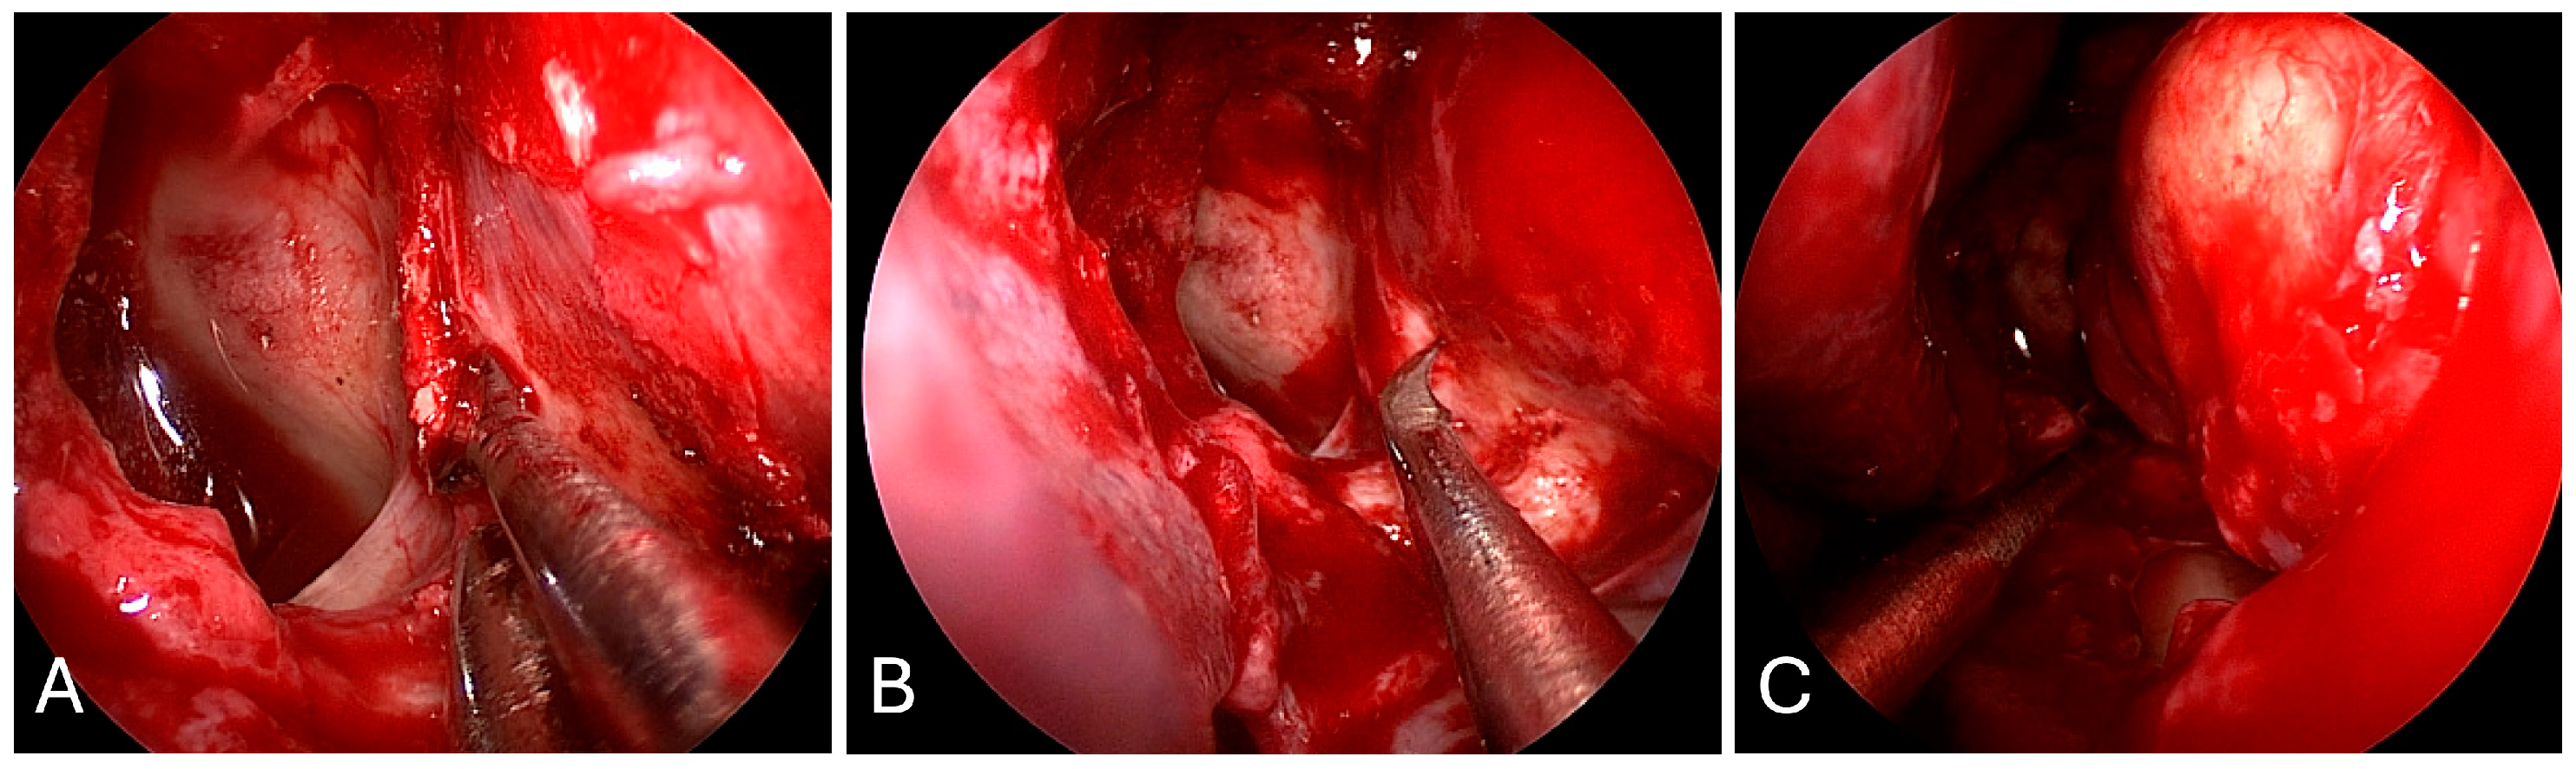

3.2.2. Illustrative Case

3.2.3. Practical Pearls

- The goals of surgical resection for metastatic lesions to the orbit are to obtain decompression of the optic apparatus and to obtain a diagnosis.

- The periorbita should be opened parallel to the medial rectus muscle to minimize inadvertent injury.

- In the medial endonasal approach, the two corridors include between the superior oblique and medial rectus muscles, as well as between the medial rectus and the inferior rectus muscles.